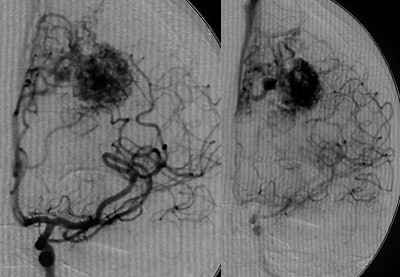

In one ICH case, a patient did not present with typical hypertensive etiology, he said. Angiography showed an occluded AVM of the middle cerebral artery, and "these patients do need endovascular treatment," he noted. "These are not patients for small stroke centers. You need experienced teams to do endovascular therapy because we can now cure 50% of patients without surgery and without radiation therapy."

| Digital subtraction angiography shows arteriovenous malformation at presentation (top, below) and two weeks postembolization (bottom) with endovascular administration of ethylene vinyl alcohol copolymer embolization agent (Onyx, Micro Therapeutics, Irvine, CA). The patient had repetitive transient ischemia attacks due to cerebral steal from the AVM. Images courtesy of Dr. Michael Forsting. |

In another example, a patient with an AVM located in the speech center of the patient's brain was a "No-touch AVM" for the neurosurgeon if not the endovascular therapist, according to Forsting. "We know these are pretty dangerous," he said. "Nowadays we go in with a catheter and we can occlude them completely." Late-venous-phase CT three weeks later showed complete occlusion, and the patient suffered no neurologic deficit.